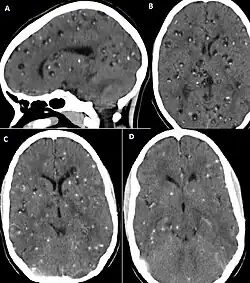

CT scan of neurocysticercosis before and after treatment

Brain CT of neurocysticercosis before (A and B) and after (C and D) treatment with albendazole[54]